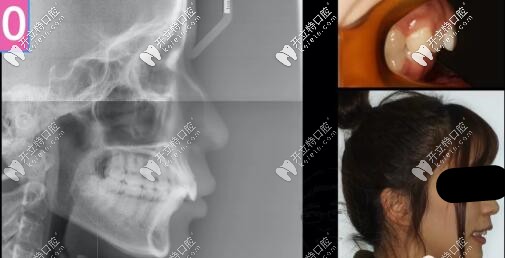

26歲女孩,來診主訴:嘴凸,大笑露牙齦,強烈訴求是解決嘴凸問題。

二類骨性齙牙正畸案例

側貌微凸,深覆合

右側磨牙尖牙關系II類,左側I類,

深覆合覆蓋5mm,下頜牙弓擁擠度5mm

骨性二類凸嘴拔牙內收案例

側位片提示:

骨性II類,均角,上前牙舌傾,下前牙唇傾前凸

計劃支抗釘整體推上頜牙列向后、壓低上牙來解決深覆合和微凸問題,選用了標準轉矩DamonQ托槽。

骨性二類齙牙單純正畸側貌效果圖

骨性二類凸嘴單純正畸牙齒內收3-4mm側貌效果圖

上前牙大量的壓低和內收,深復合改善。